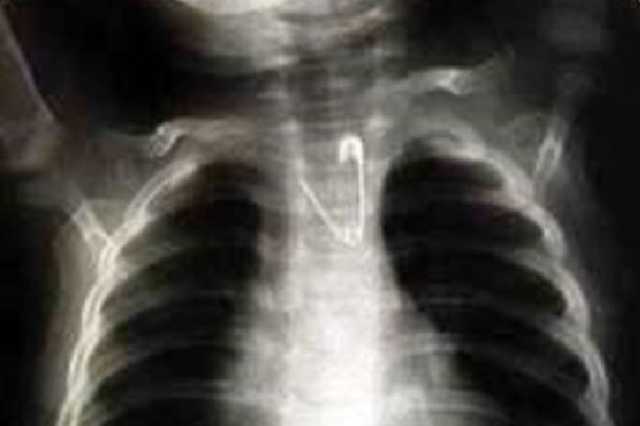

Во Львове из пищевода младенца вытащили раскрытую булавку

Львовские врачи смогли вытащит расстегнутую булавку из пищевода маленького ребенка, не нанеся ему никаких повреждений. Удивительную историю со слов врача-эндоскописта Виктора Иванцива опубликовали "Факты.

"Мне доводилось вытаскивать монеты, пуговицы, батарейки, дротики, колпачки — более 150 проглоченных предметов… Но с раскрытой булавкой я имел дело впервые. Когда девочку доставили к нам, мы тут же ввели ее в наркоз, обездвижили.

Учитывая, как именно застряла булавка в пищеводе, тащить ее вверх было совершенно немыслимо. Одно неверное движение — и пришлось бы вскрывать грудную клетку. Поначалу была мысль попробовать застегнуть манипулятором булавку, но потом пришлось отказаться от такой идеи: в узком пищеводе ребенка делать это было чрезвычайно рискованно, могло начаться кровотечение.

Поэтому мы ... протолкнули булавку в желудок, там повернули и тупым концом кверху стали очень медленно и осторожно извлекать опасный предмет из пищевода", - рассказал специалист. В Америке в таких случаях открывают уголовное дело на родителей - за небрежность. Украинские же врачи просят родителей быть более внимательными к детям, которые в определенном возрасте кладут в рот самые немыслимые предметы.